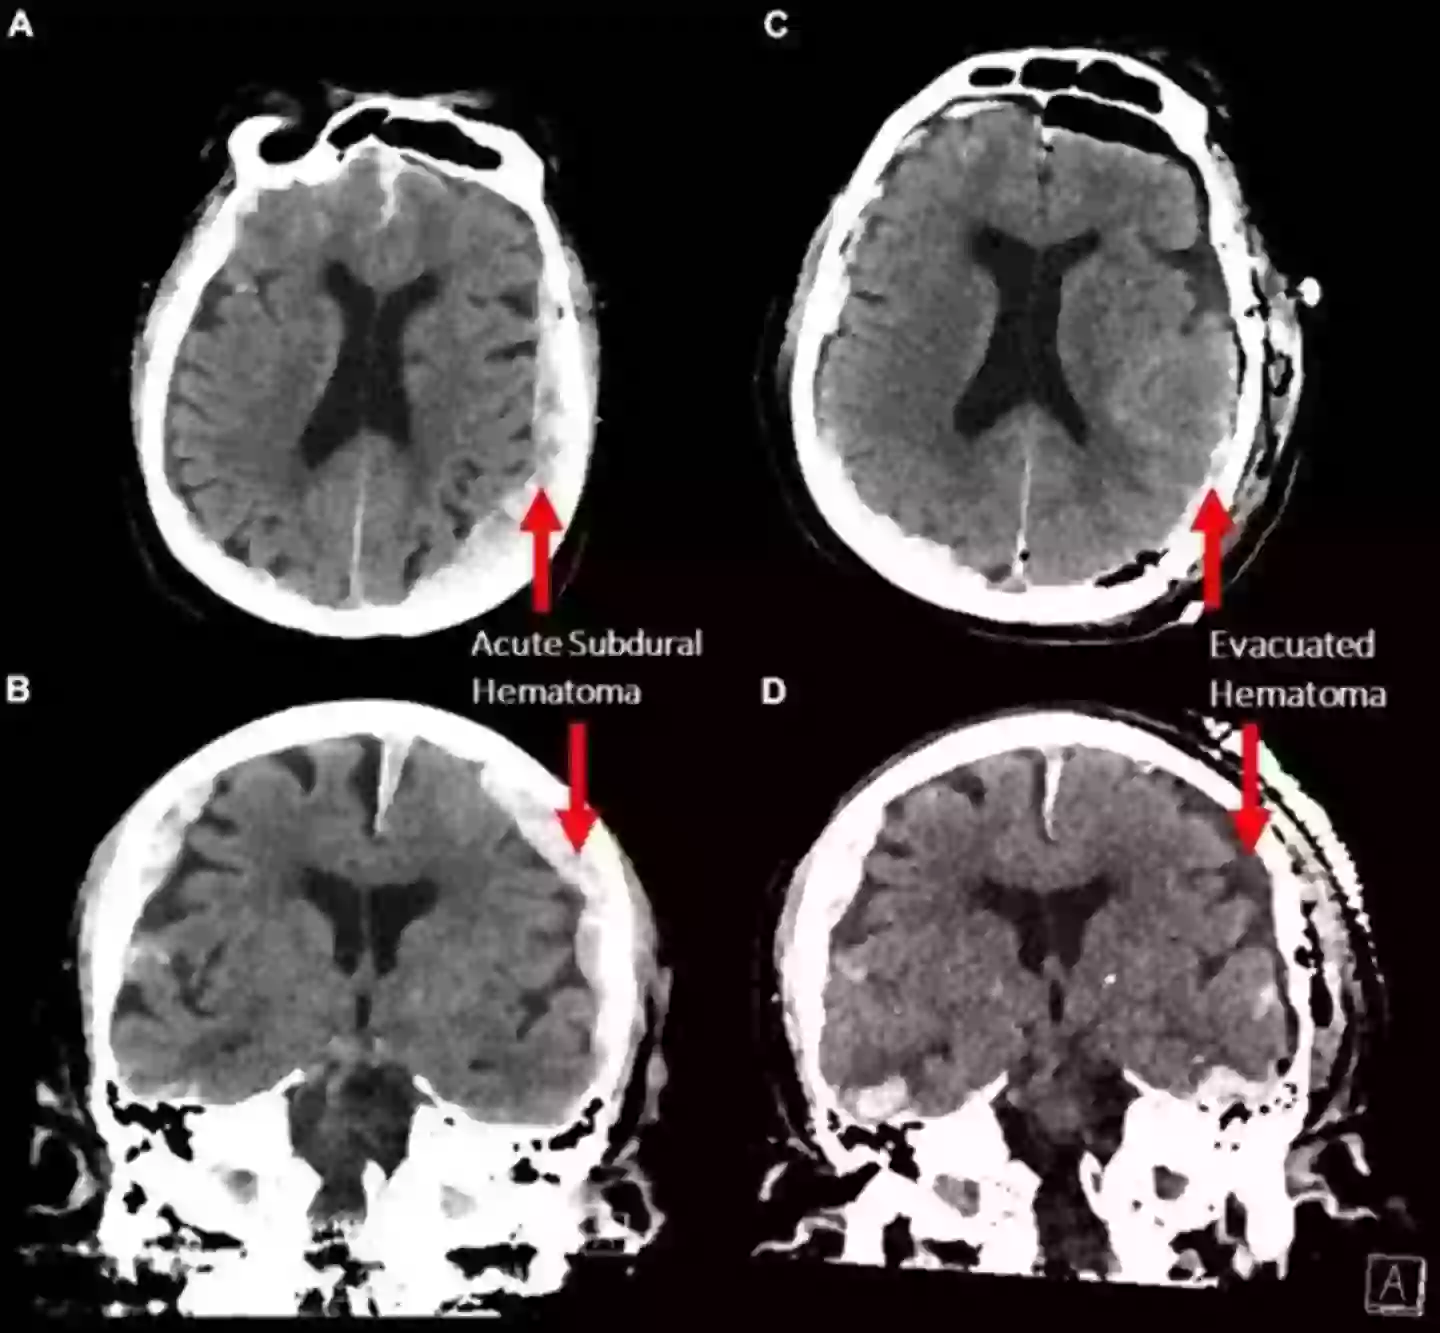

The study looked at the brain of an 87-year-old man suffering from epilepsy had been undergoing regular electroencephalography (EEG) scans at the University of Tartu, Estonia in order to detect seizures.

However, the patient had suffered a heart attack and passed away during one of the scans, which gave scientists and doctors the rare opportunity to record the brain at the moment of death.